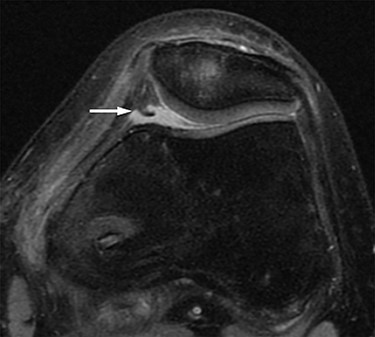

Two months postoperatively, the patient presented with the pain in the medial margin of the patella during walking and knee extension, and the pain continued when she was allowed to start rhythmic gymnastics at 6 months postoperatively. There was no evidence of swelling, crepitus and ROM restriction, and her apprehension sign was also negative. Pain was relieved by an intra-articular xylocaine injection. Postoperative MRI showed no clear injury to the cartilage of the medial PF joint, and the medial PF joint space and the size of the medial plica were almost the same as before surgery (Fig. 2). Based on these findings, left medial plica syndrome was suspected. Although the patient underwent conservative treatment consisting of analgesics and physiotherapy, there were no signs of improvement, and consent was obtained for undergoing arthroscopic surgery at 8 months after the initial surgery. Intraoperative arthroscopic findings with probing confirmed an unenlarged but hardened and thickened medial plica (Fig. 3). No injury to the patellar and femoral cartilage was observed. The synovial plica was considered the main cause of pain, and we performed a partial resection of the medial synovial plica. The pain and the tenderness at the medial margin of the patellar during walking and exercising had gradually improved after surgery. The Lysholm scale improved from 85 to 100 points. At 2 years postoperatively, the patient has currently no pain in the medial side of the patella, negative apprehension sign. She has returned to play in rhythmic gymnastics.

Intraoperative arthroscopic views. Medial synovial plica with a tight and hypertrophic margin (A). No injury to the patellar and femoral cartilage was observed (B). The synovial plica was partially removed with oval forceps (C). Image after removal (D).